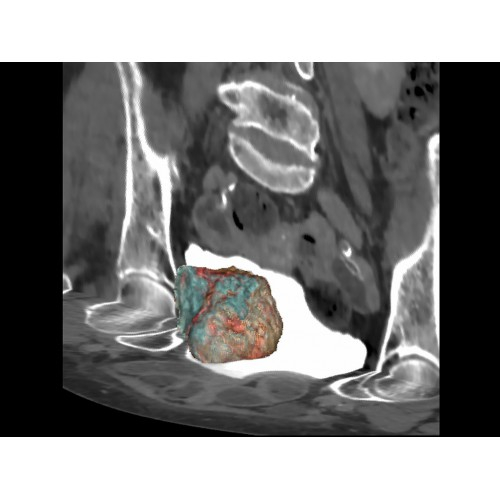

Онкология

• Раннее выявление новообразований и контроль эффективности лечения.

• Планирование лучевой терапии с высокой точностью.

• 3D-реконструкция костных структур для планирования операций.